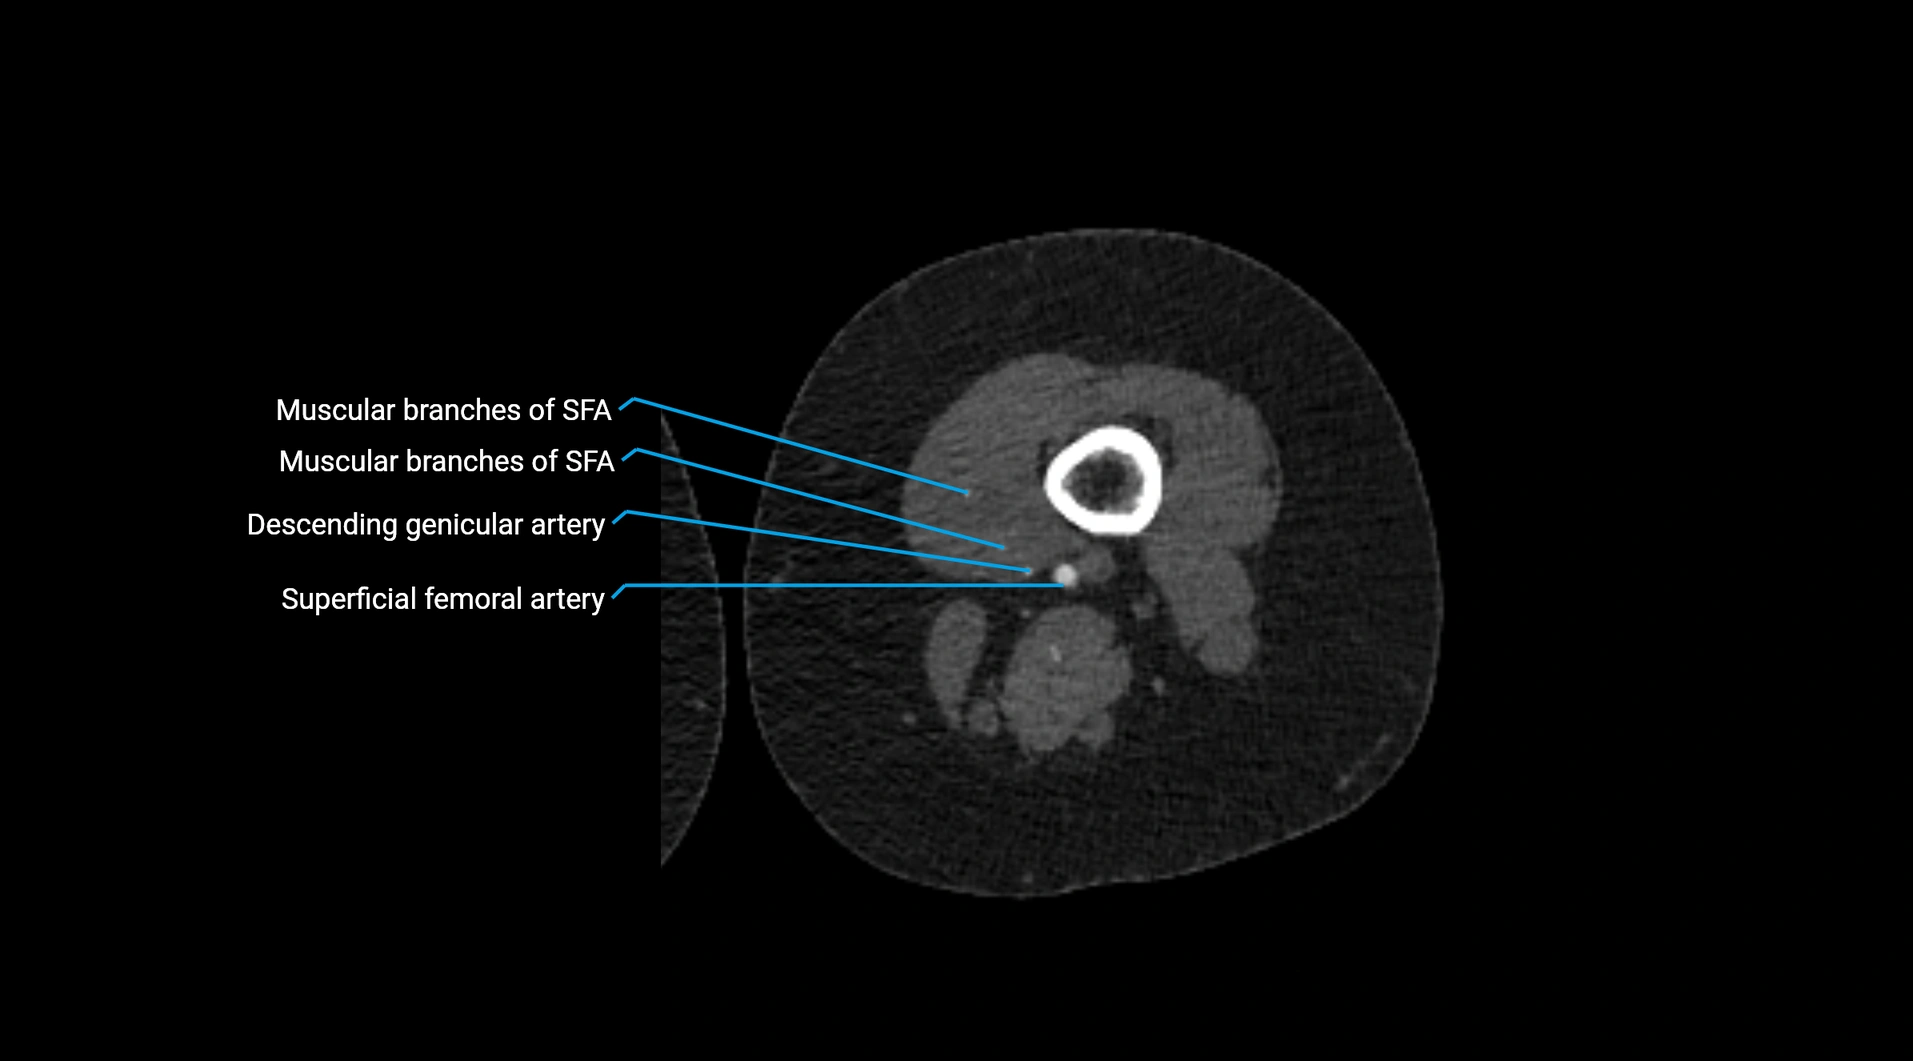

Contrast-enhanced CT (CTA):

• Gold standard for abdominal aortic imaging

• Provides excellent detail of lumen, wall, aneurysm, thrombus, and branch vessels

• Multiplanar and 3D reconstructions help in aneurysm measurement, stent graft planning, and dissection evaluation

• Detects acute rupture, traumatic injury, or occlusion with high sensitivity